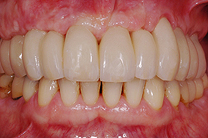

Fallbeispiel

Zum Vergrössern klicken